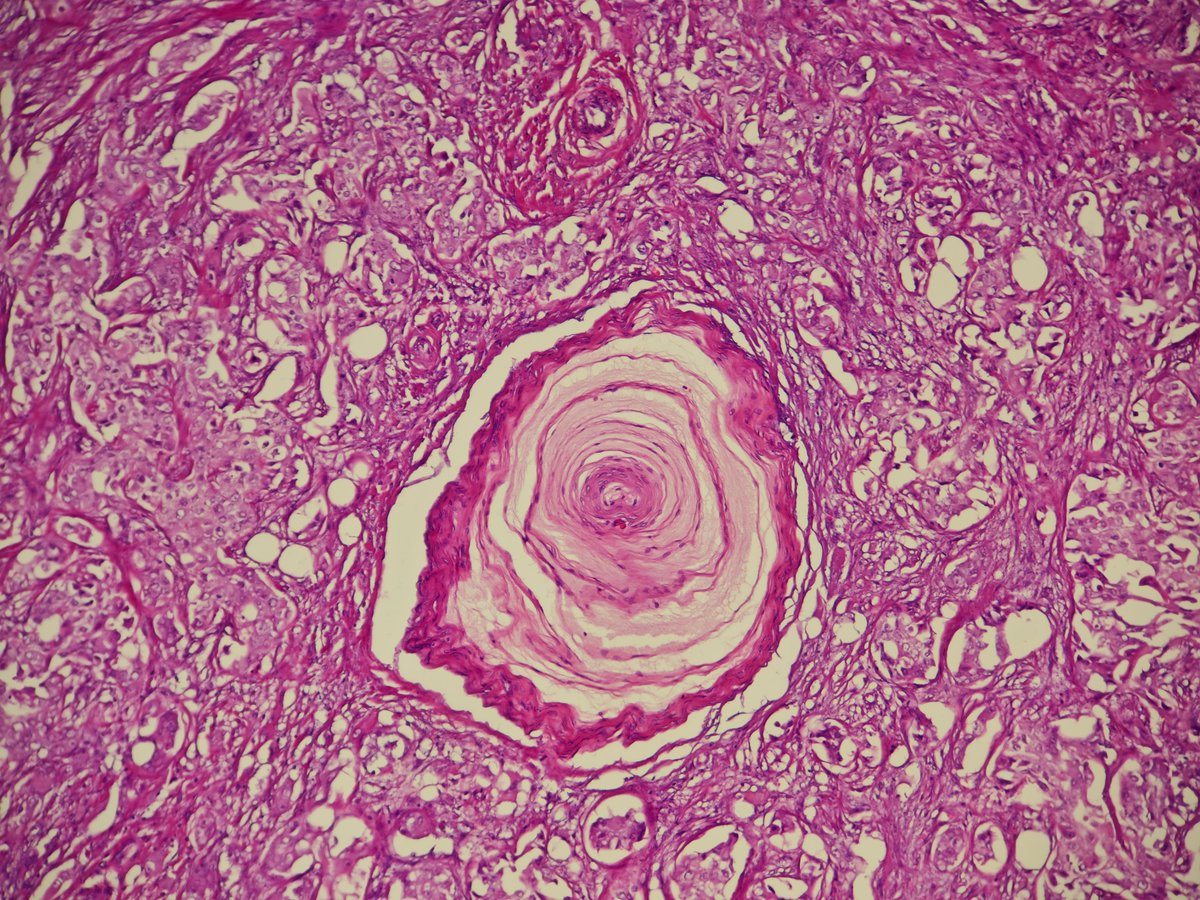

You've seen it in the prostate, now in the breast. Breast carcinoma surrounding Pacinian corpuscle. x.com/MirunaPopescu1… #PathTwitter #Breastpath

You've seen it in the prostate, now in the breast.

Breast carcinoma surrounding Pacinian corpuscle.